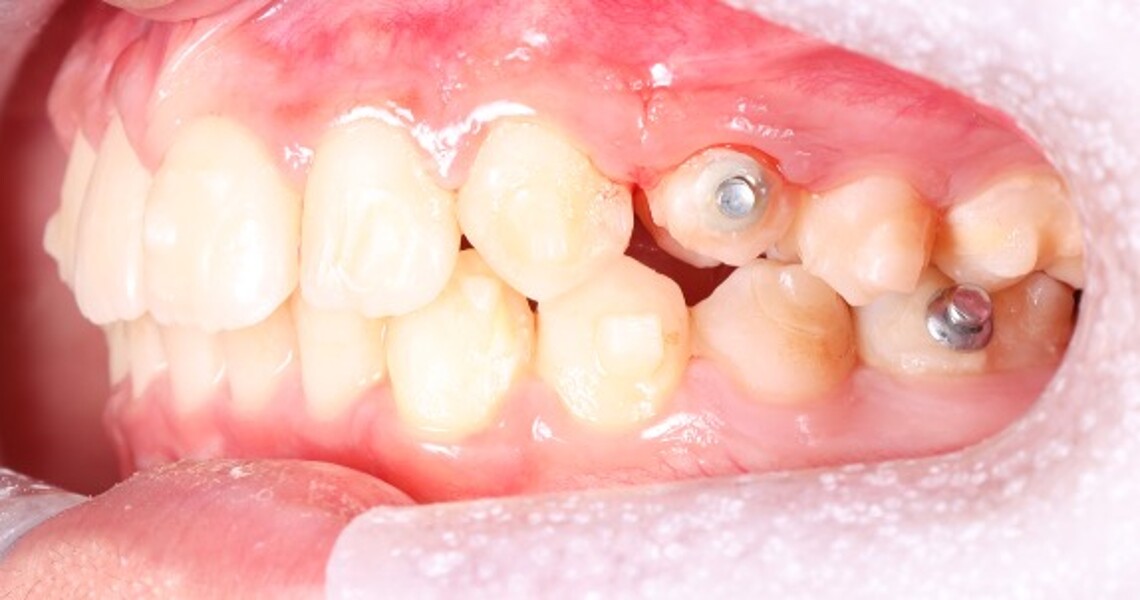

Figs. 2a–e: Pretreatment intra-oral photographs.

Fig. 2b

Fig. 2c

Fig. 2d

Fig. 2e

Clinical and radiographic evaluation revealed (Figs. 1–3):

a bilateral full-cusp Class II molar relationship;

an increased overjet of 11.7 mm;

a traumatic overbite of 7.2 mm; and

a narrow, collapsed V-shaped maxillary arch with a 2.0 mm midline deviation to the right.

Cephalometric analysis confirmed a Class II skeletal pattern primarily caused by mandibular retrusion (ANB = 5°; SNB = 69°) and showed reduced mandibular length (94 mm versus a norm of approximately 110 mm; Fig. 4; Table 1). The vertical pattern was normo-divergent (SN/GoGn = 34°). Dentoalveolar analysis showed severe maxillary incisor proclination, pronounced crowding in both arches and an accentuated curve of Spee. Soft tissue analysis showed lower lip entrapment associated with the increased overjet, contributing to an unfavourable facial profile.